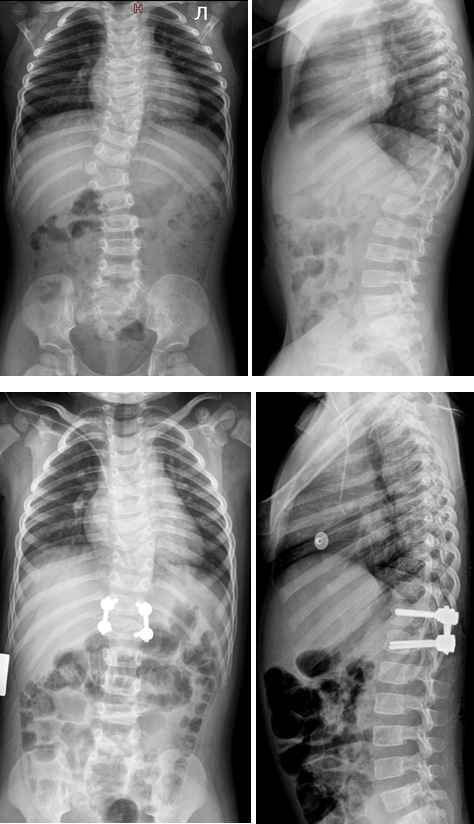

Медицина и диагностика: Аномалии ребер на рентгене